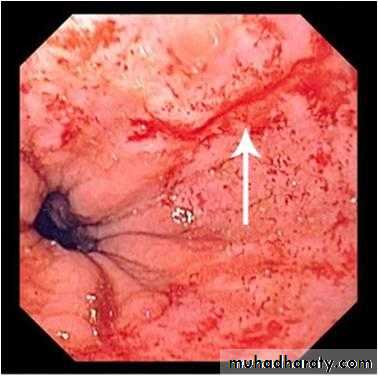

Esophagial Varices

• 100% related to portal hypertension

• Found in 90% of cirrhotics

• MASSIVE, SUDDEN, FATAL hemorrhage is the most feared consequence